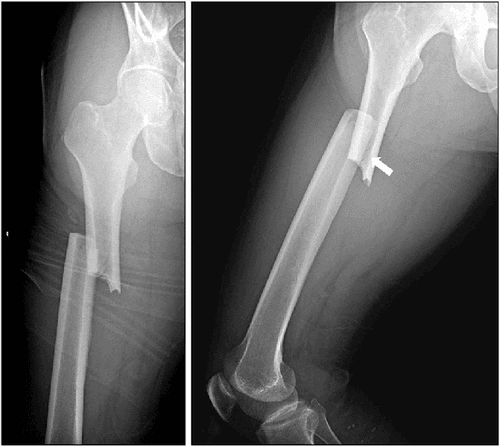

Pathological Fracture - आजारामुळे हाडे कमजोर होऊन तुटणे.

Spiral Fracture - हाडाच्या एखाद्या भागाला पीळ पडणे.